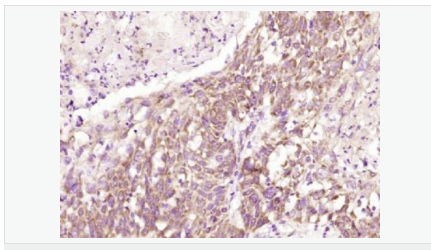

| 產(chǎn)品應(yīng)用 | WB=1:500-2000 ELISA=1:5000-10000 IHC-P=1:100-500 IHC-F=1:100-500 ICC=1:100-500 IF=1:100-500 (石蠟切片需做抗原修復) not yet tested in other applications. optimal dilutions/concentrations should be determined by the end user. |

| 產(chǎn)品介紹 | This gene encodes a type I transmembrane protein and is a tumor-specific endothelial marker that has been implicated in colorectal cancer. The encoded protein has been shown to also be a docking protein or receptor for Bacillus anthracis toxin, the causative agent of the disease, anthrax. The binding of the protective antigen (PA) component, of the tripartite anthrax toxin, to this receptor protein mediates delivery of toxin components to the cytosol of cells. Once inside the cell, the other two components of anthrax toxin, edema factor (EF) and lethal factor (LF) disrupt normal cellular processes. Three alternatively spliced variants that encode different protein isoforms have been described. [provided by RefSeq, Oct 2008] Function: Plays a role in cell attachment and migration. Interacts with extracellular matrix proteins and with the actin cytoskeleton. Mediates adhesion of cells to type 1 collagen and gelatin, reorganization of the actin cytoskeleton and promotes cell spreading. Plays a role in the angiogenic response of cultured umbilical vein endothelial cells. Subunit: Interacts with gelatin and type 1 collagen. Interacts with the actin cytoskeleton. Binds to the protective antigen (PA) of Bacillus anthracis. Binding does not occur in the presence of calcium. Subcellular Location: Cell membrane; Single-pass type I membrane protein. Cell projection, lamellipodium membrane; Single-pass type I membrane protein. Cell projection, filopodium membrane; Single-pass type I membrane protein. Note=At the membrane of lamellipodia and at the tip of actin-enriched filopodia. Colocalizes with actin at the base of lamellipodia. Tissue Specificity: Detected in umbilical vein endothelial cells (at protein level). Highly expressed in tumor endothelial cells. DISEASE: Defects in ANTXR1 are associated with susceptibility to hemangioma capillary infantile (HCI) [MIM:602089]. HCI are benign, highly proliferative lesions involving aberrant localized growth of capillary endothelium. They are the most common tumor of infancy, occurring in up to 10% of all births. Hemangiomas tend to appear shortly after birth and show rapid neonatal growth for up to 12 months characterized by endothelial hypercellularity and increased numbers of mast cells. This phase is followed by slow involution at a rate of about 10% per year and replacement by fibrofatty stroma Similarity: Belongs to the ATR family. Contains 1 VWFA domain. SWISS: Q9H6X2 Gene ID: 84168 Database links: Entrez Gene: 84168 Human Entrez Gene: 69538 Mouse Omim: 606410 Human SwissProt: Q9H6X2 Human SwissProt: Q9CZ52 Mouse Unigene: 165859 Human Unigene: 232525 Mouse Unigene: 41192 Rat Important Note: This product as supplied is intended for research use only, not for use in human, therapeutic or diagnostic applications. |